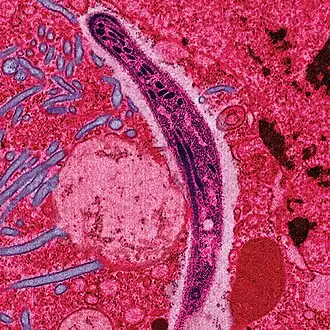

Sporozoarele reprezintă un grup de protiste asemănătoare animalelor, ce fac parte din încrengătura Apicomplexa. Sunt cunoscute în jur de 25.000 specii. Acestea nu prezintă organite de locomoție, precum cilii sau flagelii. Hrănirea este exclusiv heterotrofă. Toate sporozoarele sunt organisme parazite, care își dobândesc nutrienții pe seama altor organisme. Au un ciclu de viață complex, care implică mai multe gazde. Sunt unicelulare.

Acestea posedă un apicoplast și un complex apical, care le permite să infecteze gazdele. Complexul apical constă din:

- Conoidă;

- Rhoptrie;

- Fibrile;

- Microtubuli;

- inele polare;

- Vacuole, microneme, precum și o membrană trilamenară.